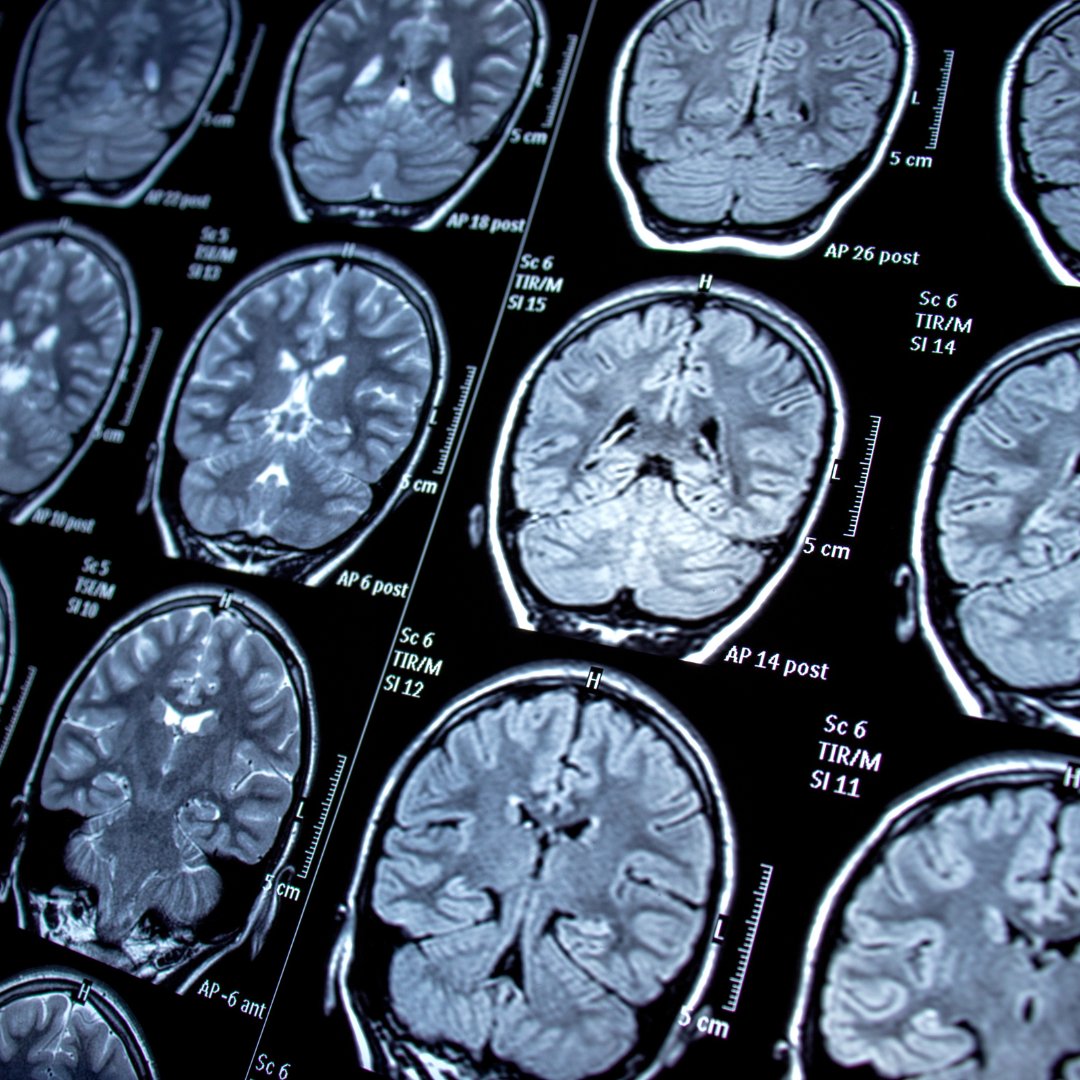

When someone experiences a seizure due to a glitch in brain signals, it's called epilepsy. Seizures can vary in terms of frequency and intensity for each person. Sometimes there's a known cause for the issue, but other times it's a mystery. Doctors often prescribe anti-epileptic drugs, but they don't work well for about 35% of patients. That's why people start looking for alternative treatments. In the book "Complementary and Alternative Therapies for Epilepsy," three medical professors talk about different alternative approaches. They cover things like Ayurveda, acupuncture, neurofeedback therapy, and meditation. The book also brings up some interesting points that make a strong case for considering hypnosis as a serious option for managing epilepsy.

On another note, clinical hypnosis can be beneficial in treating epilepsy. Epilepsy affects the brain's electrical signals and can significantly impact someone's daily life. People often believe that certain actions or stress can trigger seizures. Clinical hypnosis can teach patients how to better manage their behaviour and reduce seizures.